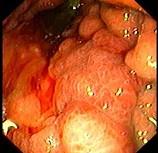

问题 男性患者,45岁,平素身体健康,近2个月出现上腹饱胀不适,偶有隐痛,伴纳差,近2天有黑粪,胃镜如图。关于本病,下列说法正确的有 ( )

选项 A.可诊断为胃癌 B.可诊断为胃间质瘤 C.处于早期 D.处于进展期 E.应马上手术治疗

答案 ADE